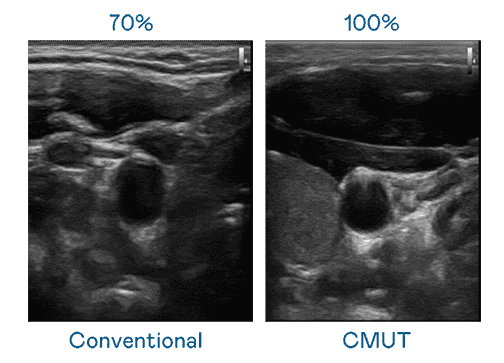

CMUT 技术是一种用电容式微机电元件来产生超音波讯号的技术。。。。与传统 PZT 压电式技术相比,,CMUT 频宽增加 30%,,更宽频的超音波讯号让影像解析度大幅提升,,,,是实现高影像品质医疗超音波扫描、、、、促进精准医疗发展的关键技术。。。。

大频宽带来超清晰影像

超音波影像的解析度高低,,,,首先取决于探头能发出的讯号频宽。。尊龙集团 CMUT 可提供高清晰的超音波讯号,,提供高频宽、、、、高灵敏度、、、、影像纹理细节更高的超音波影像,,协助医护人员缩短影像判读时间及利用精准的医疗影像进行诊断。。